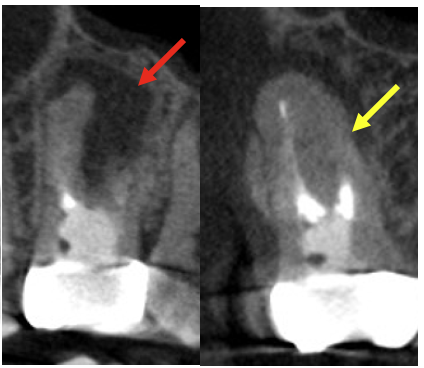

術前、右上2に大きな透過像(黄色矢印、炎症の黒い影)と左上1にも透過像(赤矢印)が見られます。腫れの原因は、歯髄壊死と根尖性歯周炎と診断し、まずは根管治療を行いました。左上1の根尖も透過像(緑矢印)がありましたが、歯髄の反応は正常でしたので歯髄壊死とは診断せず治療は行いません。

• 根管治療後4ヶ月、左上1の透過像(赤矢印、黒い影)は小さくなり治癒傾向が確認できますが、右上2(赤矢印)は以前より広がってきていて、腫脹の再発がありました。非治癒判定となり、次の治療法として歯根端切除術を行うこととなりました。歯根端切除術を行わない医院ではこの時点で抜歯が宣告されてしまうでしょう。

• 歯根端切除前と術後1年のCBCT画像、病変はなくなり骨の再生を認め治癒が確認されました。

• 別の角度のCBCT画像、骨の壁が全くない状態から1年でかなりの骨の再生が見られます。

• 別の角度のCBCT画像、骨の壁の再生がはっきりとわかります。